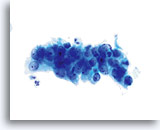

Adenocarcinoma in situ

Unterschiedlich große, dichte, hyperchromatische Zellverbände, die in der Übersichtsvergrößerung auffallen, machen eine genauere Beurteilung nötig.

20x

Adenocarcinoma in situ

Unterschiedlich große, dichte, hyperchromatische Zellverbände, die in der Übersichtsvergrößerung auffallen, machen eine genauere Beurteilung nötig.

20x